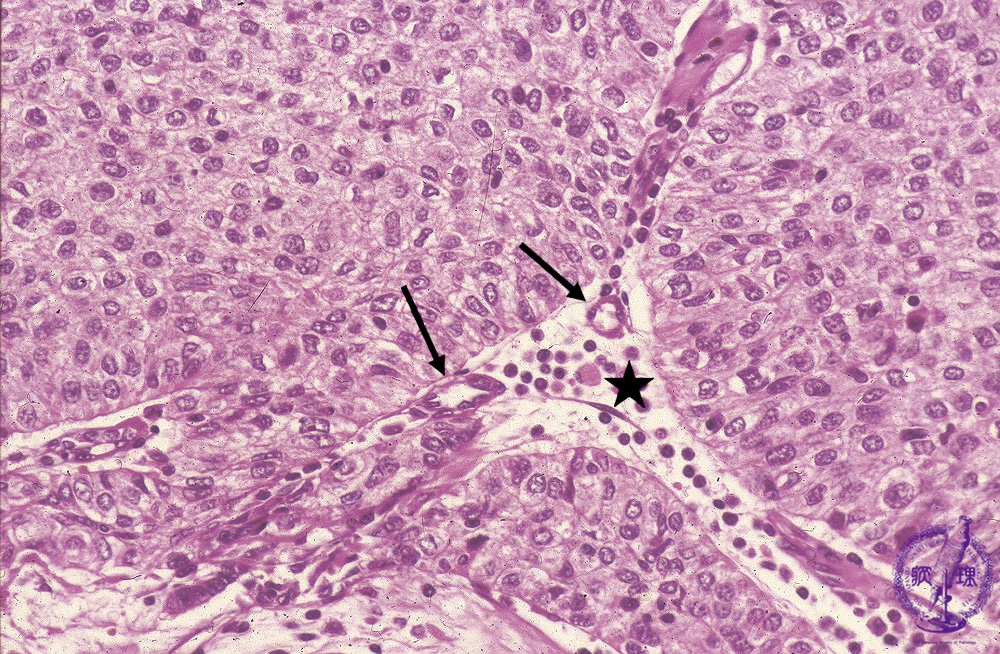

Microscopic view (high power view): Type B3 thymoma (epithelial thymoma) (WHO classification). Large, polygonal epithelial tumor cells grow in sheets without infiltrating lymphocytes. The perivascular spaces (★) seen centrally surrounding small capillaries (arrow) are a finding specific to thymoma.